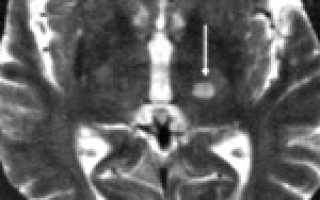

Термин « инфаркт мозга» приобретает все большее распространение с широким применением методов нейровизуализации, позволяющих уточнить локализацию и размеры ишемического очага и предположить его природу. Однако по своему смыслу термин «инфаркт мозга» не вполне эквивалентен термину «ишемический инсульт».

Ишемический инсульт – клиническое выражение инфаркта мозга, а инфаркт мозга – морфологический субстрат ишемического инсульта.

— КТ и/или МРТ-ангиография;